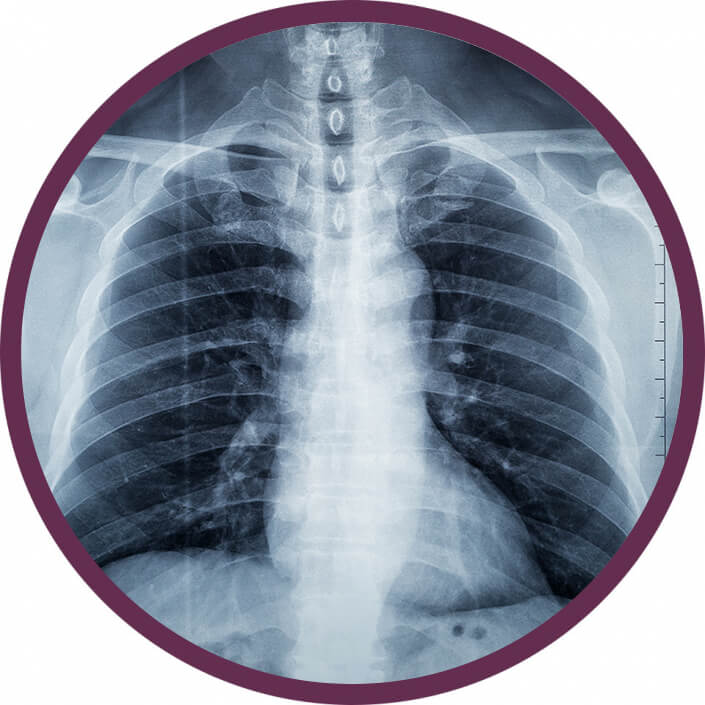

Alacsony dózisú tüdő CT

Tüdő CT

Az alacsony dózisú mellkas CT-vizsgálatok nagyon fontos szerepet töltenek be a COVID-19 betegség gyógyításában, hiszen megerősíthetik a koronavírus-fertőzés gyanúját, így információt nyújtva a betegség lefolyásáról, támogatva ezzel a gyógyítás folyamatát.

ALACSONY DÓZISÚ TÜDŐ CT

Miért válassza ezt az eljárást?

Az alacsony dózisú mellkas CT egy optimalizáltan minimális sugárterheléssel elvégezhető 1-2 perces nem invazív diagnosztikus eljárás. Az alacsony dózisú mellkas CT vizsgálat alkalmas a krónikus obstruktív légúti tüdőbetegségek, mint a krónikus bronchus gyulladás (bronchitis), valamint a tüdő tágulat (emphysaema) és a tüdőfibrózis hatékony kimutatásra és követésére. Emellett az alacsony dózisú mellkas CT hatékony eljárás az alsó légutakat érintő bakteriális vagy vírusos tüdőgyulladás elkülönítésében, (Pl: SARS-kov2)! Az eljárásnak – a gyorsasága mellett – további nagy előnye, hogy kontrasztanyag adásra nincs szükség és a röntgenfelvételen kis méretük miatt nem látható gócok, daganatok is felismerhetők a CT vizsgálattal. Ezáltal olyan daganatos betegségek is észlelhetők korai, tehát még jól kezelhető illetve teljesen gyógyítható tünetmentes fázisban, mint például a tüdőrák. Ez egy hatalmas áttörés, hiszen a tüdőrák előfordulását és halálozási arányát tekintve Magyarország a világelsők között van.

NE VÁRJA MEG, HOGY TÚL KÉSŐ LEGYEN! CSELEKEDJEN MOST!

JELENTKEZZEN BE NATÍV MELLKAS CT VIZSÁLATRA!

Tüdő CT

Hogyan végezzük a vizsgálatot?

A CT-készülékünk egy nagy, vastag gyűrűhöz hasonlít, melynek aljában egy asztal van, ami mozog. Ön ezen az asztalon fekszik mozdulatlanul, miközben a felvételeket készítünk. A vizsgálószerkezet működése közben zúgó, búgó hangot ad ki, de ettől nem kell megijedni, hisz a vizsgálat fájdalommentes. A vizsgálat közben Ön folyamatosan audiovizuális kapcsolatban van az operátorral.

Miért válassza ezt a vizsgálatot?

A kontrasztanyag adásával kombinált mellkas CT vizsgálat elvégzése elsősorban tüdőembólia gyanúja esetén, illetve korábban igazolt tüdőgóc, krónikus gyulladás, kerekárnyék vagy daganat gyanúja esetén indokolt, az elváltozás természetének és a nyirokcsomó érintettség megítélése céljából!

Mikor nem végezhető el a vizsgálat?

A CT vizsgálat röntgensugarakkal történik, ezért terhesség illetve szoptatás ideje alatt nem ajánlott. Kiskorú/gyermek esetében nyomós indikációval vagy szakorvosi beutalóval végezhető el a vizsgálat. Kontrasztanyag adása kerülendő kontrasztanyag érzékenység, súlyosan beszűkült veseműködés esetén és cukorbetegségben alkalmazott metformin tartalmú gyógyszerek szedése esetén.